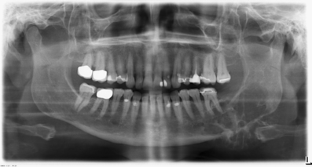

We describe a 64-year-old female patient with a cystic tumor mass of the mandible leading to pathologic bone fracture. X-ray analysis was suggestive for aneurysmatic bone cyst. A segment resection was performed.

Fig. 1